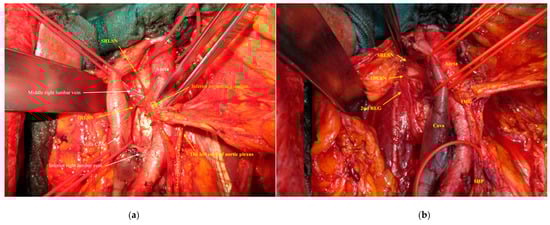

2.2. Dissection of the Right Cord of the Aortic Plexus

2.3. Dissection of the Left Cord of the Aortic Plexus